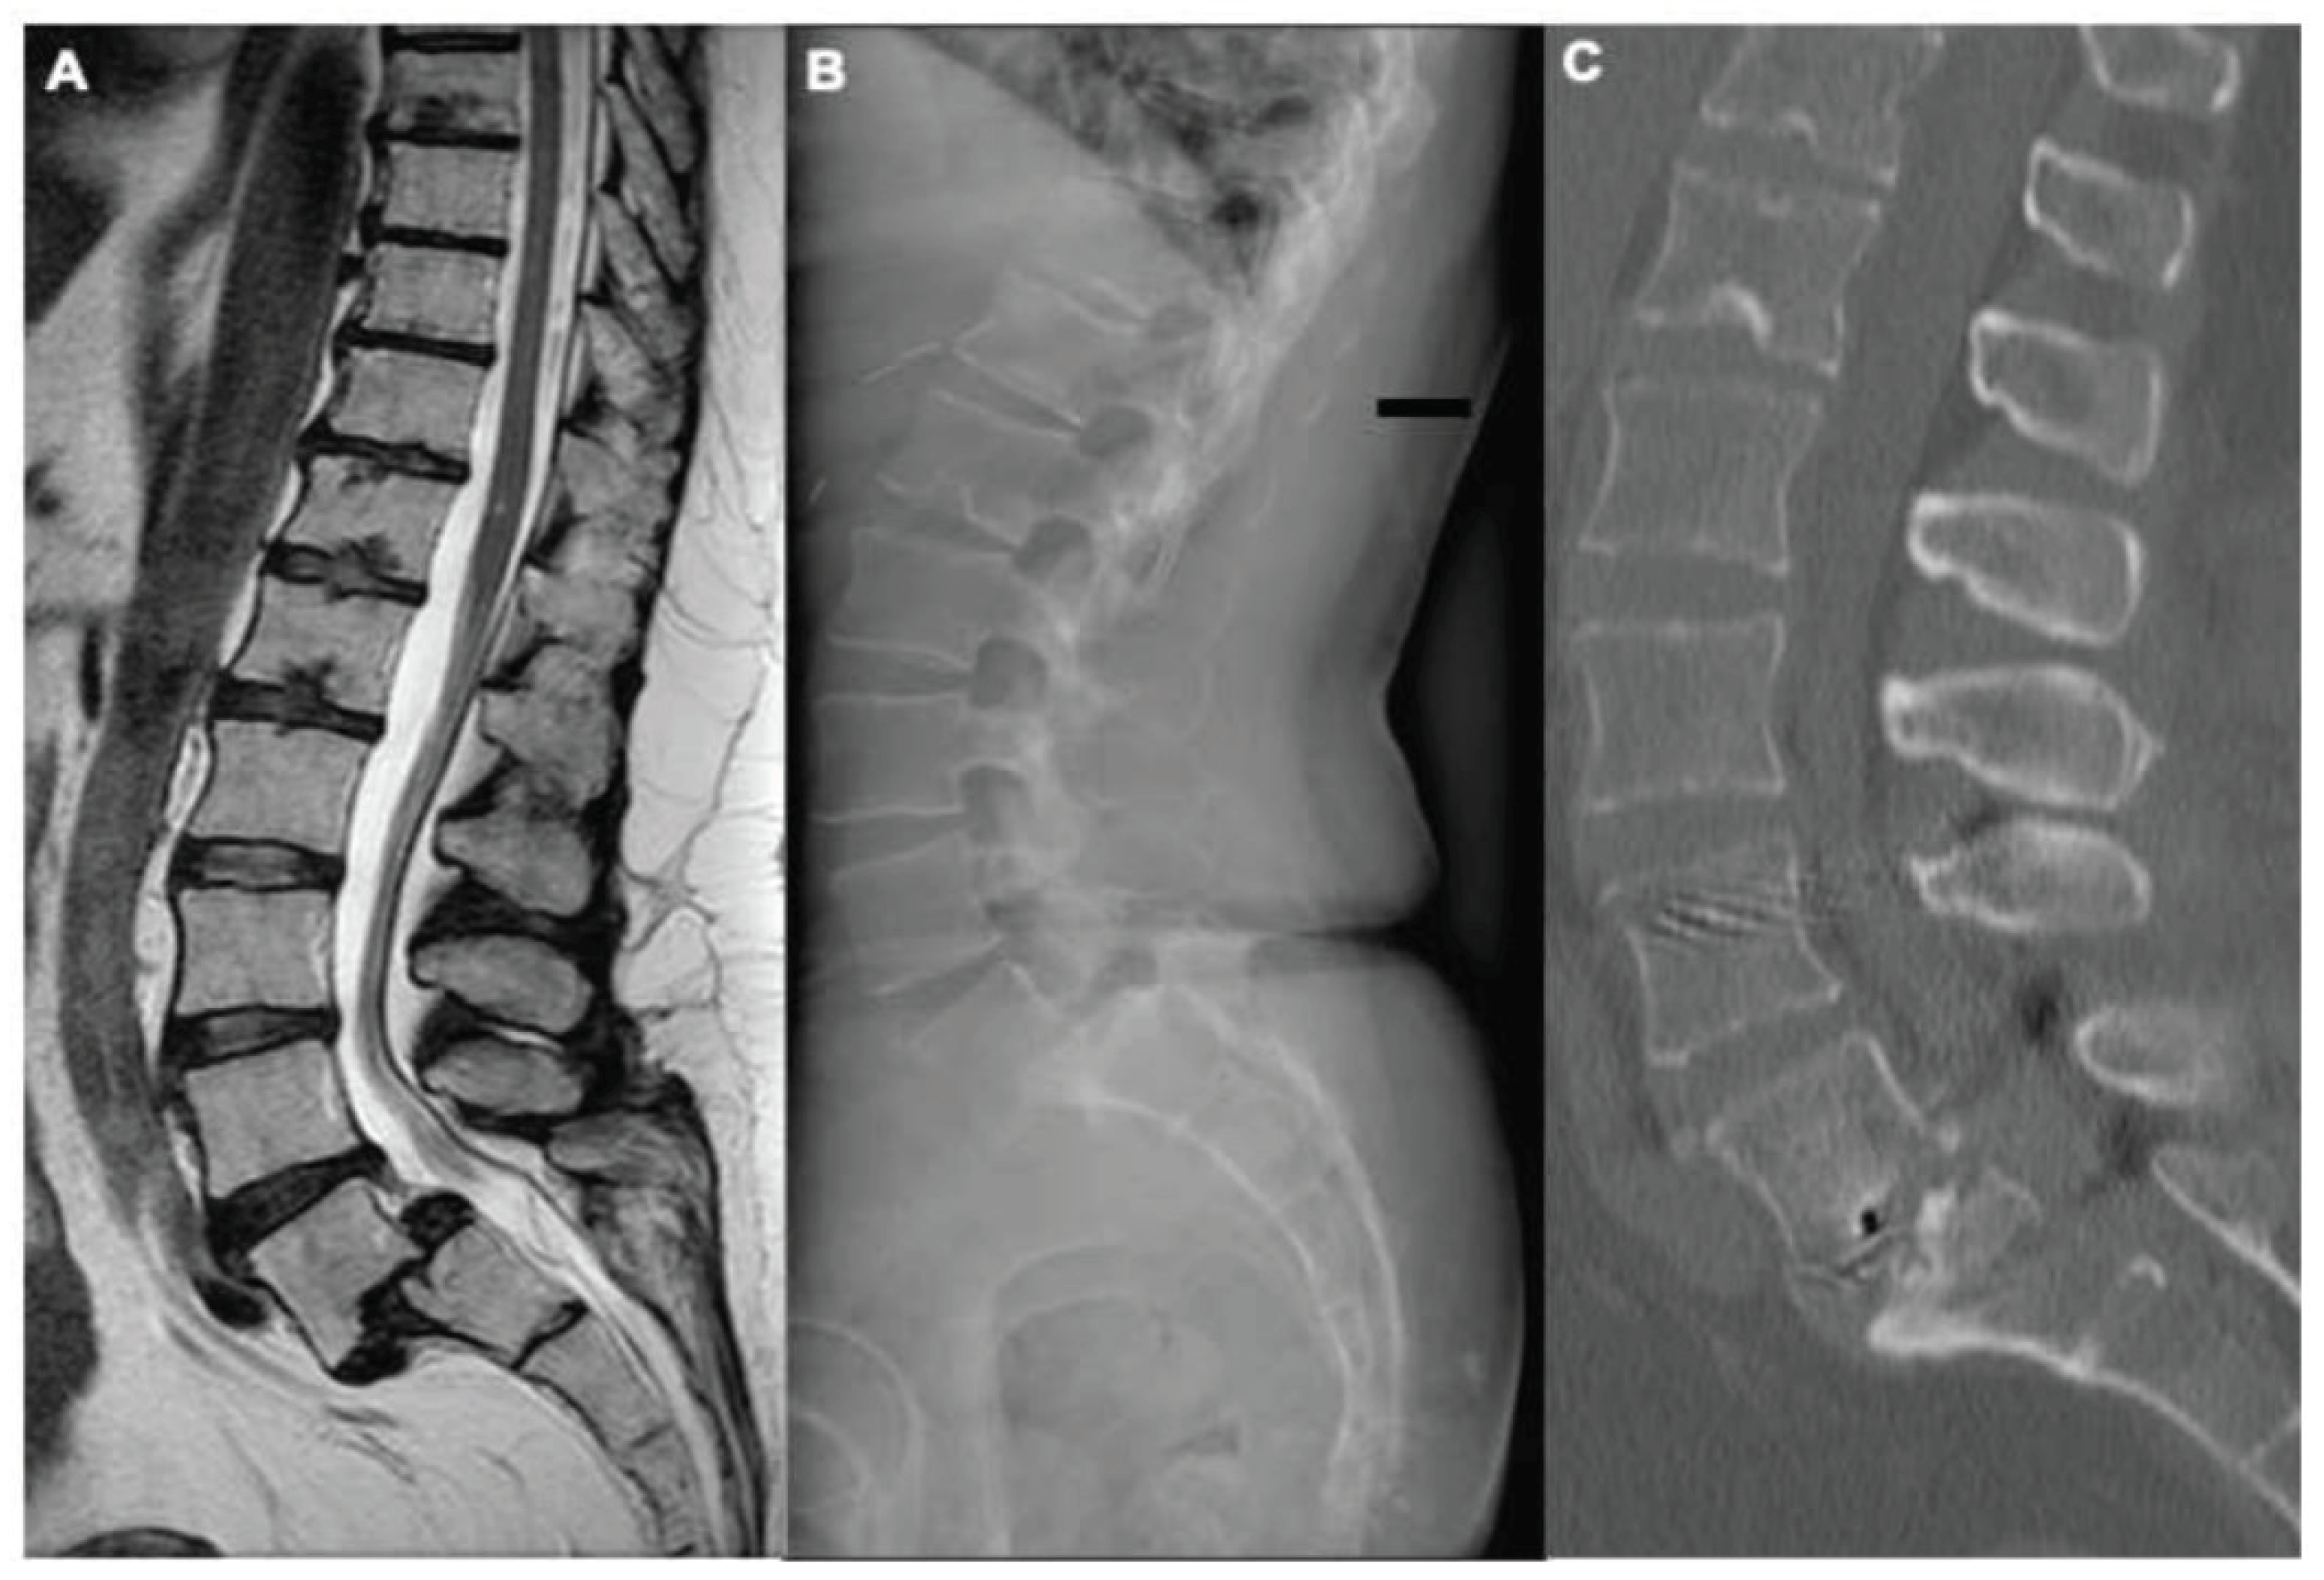

The mean changes at last follow-up evaluation were slippage 65 (±5)% (p = 0,02), slip angle 12 (±7) degrees (p=0,01), pelvic tilt 7 (±8) degrees (p<0,01). The sagittal vertical axis (SVA) was found in the range of normality [18] preoperatively and two years after surgery in all patients. No significative differences were found comparing pre- and post-operative thoracic kyphosis, lumbar lordosis, and pelvic incidence values. An illustrative case is showed in Figure 1. The univariate analysis showed that a slip angle > 10° (Figure 2) was the only independent factor, in our cohort of patients, in determining higher VAS-b and ODI scores (p=0,001 and p=0,03 respectively).

Figure 1. Illustrative case. We present the case of a 17-year-old female, referred to our institution for medical-resistant low-back pain and severe bilateral L5 radiculopathy. The preoperative MRI (A) and x-Rays (B) confirmed the diagnosis of L5-S1 high-grade isthmic spondylolisthesis. This young patient underwent bilateral minimally invasive TLIF. The postoperative CT scan (C) confirmed the segmental deformity correction, the PLIF cages positioned in the L5-S1 disc space, and the bilateral pedicle screws on L4-L5-S1. This patient was mobilized on the first postoperative day, without external orthosis, and discharged in 3 days.